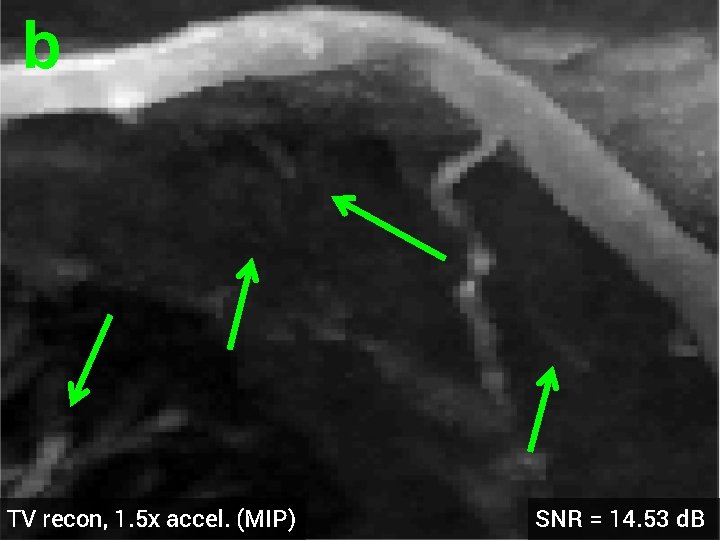

3 -D Compressed Sensing MRA § 512 x 76 voxel MRA dataset obtained from physiobank (see ref. [6]) § Simulated single coil acquisition § Retroactively undersampled at 1. 5 -fold acceleration § Random Gaussian sampling of k-space § 5 d. B additive Gaussian noise § Optimized regularization parameter MIP of original MRA dataset

b a TV recon, 1. 5 x accel. (MIP) SNR = 14. 53 d. B

b TV recon, 1. 5 x accel. (MIP) SNR = 14. 53 d. B

3 -D Quantitative Results Table 3: 3 -D Comparisons. SNR (in d. B) of recovered images with optimal reg. param. Denoising Cell 1 Cell 2 Deblurring Cell 1 CS-MRI Cell 2 Cell 3 Angio, acc=5 Angio, acc=1. 5 Cardiac TV 17. 12 16. 25 19. 02 16. 43 14. 50 13. 87 14. 53 18. 37 HDTV 2 17. 25 16. 70 19. 15 16. 60 14. 87 14. 23 15. 11 18. 56 HDTV 3 17. 68 17. 14 19. 73 17. 43 15. 23 14. 01 14. 70 18. 50 § HDTV outperforms TV in all experiments § HDTV 3 better for denoising and deblurring § HDTV 2 better for CS-MRI